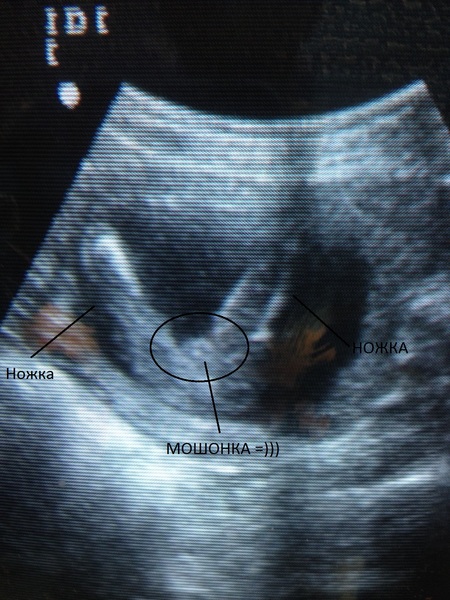

À quoi ressemblent les estomacs à la dix-huitième semaine? C'est différent pour tout le monde. Certaines mères semblaient avaler une balle, tandis que d'autres semblaient s'étirer de haut en bas. C'est bon. Parfois, ils essaient de deviner par la forme de l'abdomen si une fille ou un garçon va naître.Et pourtant, seul un spécialiste en échographie peut vous dire avec certitude si cette semaine vous est prescrit une telle étude et que l'enfant veut partager un secret.

Photos d'échographie